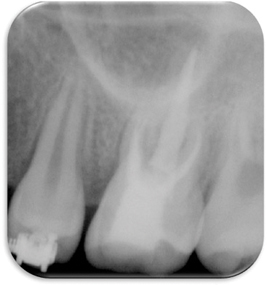

Figure 7

Periapical x-ray after canal filling.